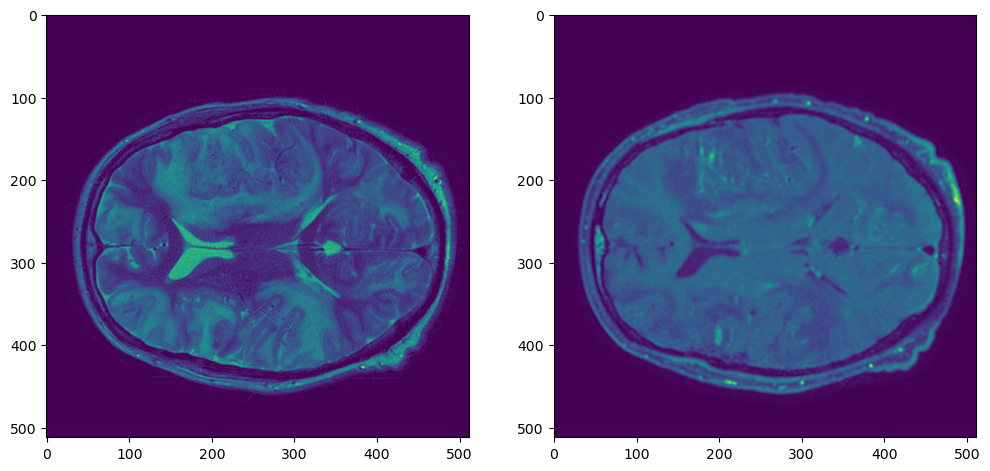

plt.figure(figsize=(12,6))

plt.subplot(121)

plt.imshow(t1_nib_array[:,:,t1_nib_array.shape[2]//2])

plt.subplot(122)

plt.imshow(t2_nib_array[:,:,t2_nib_array.shape[2]//2])

t1t2

plt.imshow(t1_resampled_array[:,:,t1_resampled_array.shape[2]//2])

t1t2resampled

Работает довольно медленно, но есть решение быстрее.